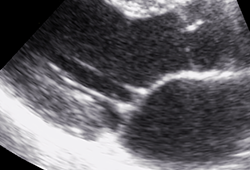

Parasternaler Längsschnitt

Grundlagen & Standards

Gerätebasis, Bildoptimierung, Standardschnittebenen, Normalbefunde, Messungen.

Parasternal, apikal, subkostal – Orientierung sicher